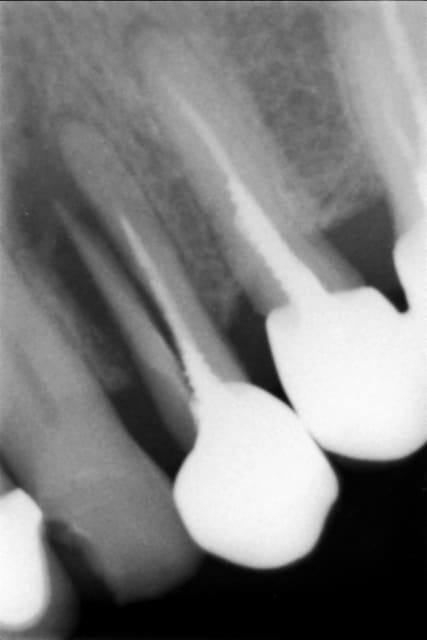

Un "vieux cas" LEONE qui se passe bien malgré des conditions de départ et de chirurgie pas au mieux! 4 ans déjà et aspect sympa très stable dans le temps. une de mes extractions implantation immédiate en site "pas idéal".La chronologie en rx.

Janvier 2008 vzunxr - Eugenol

Octobre 2008 ehmsfj - Eugenol

Mars 2008 jt5qx2 - Eugenol

Novembre 2011 ane4ar - Eugenol